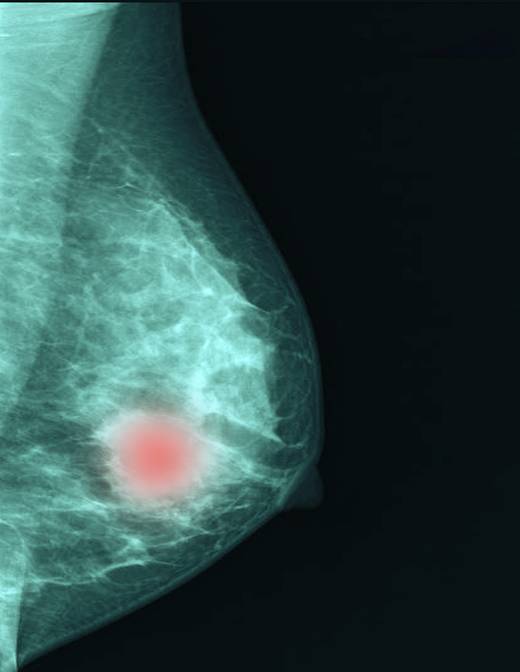

유방암 중에서도 치료가 까다롭기로 알려진 유형이 '삼중음성(Triple Negative) 유방암'이다.

삼중음성 유방암은 에스트로겐·프로게스테론 등 여성호르몬 수용체와 HER2 수용체가 모두 없는 형태로, 표적 항암제가 작용하는 3가지 수용체가 모두 없는 유형이라 일반 유방암보다 치료가 어렵다.

유방암 중에서도 치료가 까다롭기로 알려진 유형이 '삼중음성(Triple Negative) 유방암'이다. 그런데 이 암에서 유전자와 단백질 정보를 함께 분석하면 항암치료 효과를 정확하게 예측할 수 있다는 연구 결과가 나왔다. 환자마다 다른 치료 반응을 사전에 가늠해 개인 맞춤 치료로 이어질 수 있는 기반이 마련됐다는 점에서 주목된다.

삼중음성 유방암은 에스트로겐·프로게스테론 등 여성호르몬 수용체와 HER2 수용체가 모두 없는 형태로, 표적 항암제가 작용하는 3가지 수용체가 모두 없는 유형이라 일반 유방암보다 치료가 어렵다. 전체 유방암의 15% 수준으로 비율이 높지는 않지만, 예후가 가장 좋지 못하고 전이·재발 위험이 큰 유형이다. 다른 유방암보다 진행 속도가 빠르고 재발 위험이 크다. 수술 전 선행 항암 화학요법을 먼저 시행하는 경우가 많지만, 환자마다 치료 반응 차이가 커 예측하기가 어렵다.